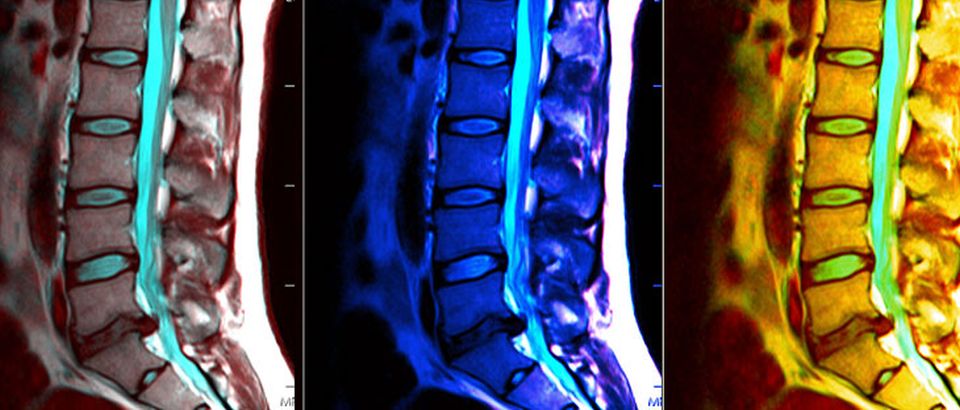

Томография позвоночника представляет собой исследование спины, благодаря которому врачи получают послойное изображение внутренней структуры тела человека в этой области. Относится к неинвазивным методам исследования организма, базированным на электромагнитном (МРТ) или рентгеновском излучении (КТ).

Разные методы выполняются с одинаковой целью, заключающейся в пошаговом сканировании тела, построении снимков в разных проекциях, создании 3D модели органов. Но их специфика работы имеет отличия, и они влияют на результаты осмотра.

Возможности КТ обусловлены свойствами рентгеновских лучей, она предоставляет качественные снимки костных структур. Проходит процедура за считанные минуты. Доза облучения совсем мизерная, но часто осматривать пациента этим методом не желательно.

Основой МРТ является мощное магнитное поле и определённая комбинация электромагнитных волн. Это отличный метод для оценки мягких тканей, патологий в них, диагностики травм связок или суставных повреждений. Длительность осмотра может составлять от 30 минут до 1,5 часов. МР обследование абсолютно безопасно для организма и проводить его можно регулярно.